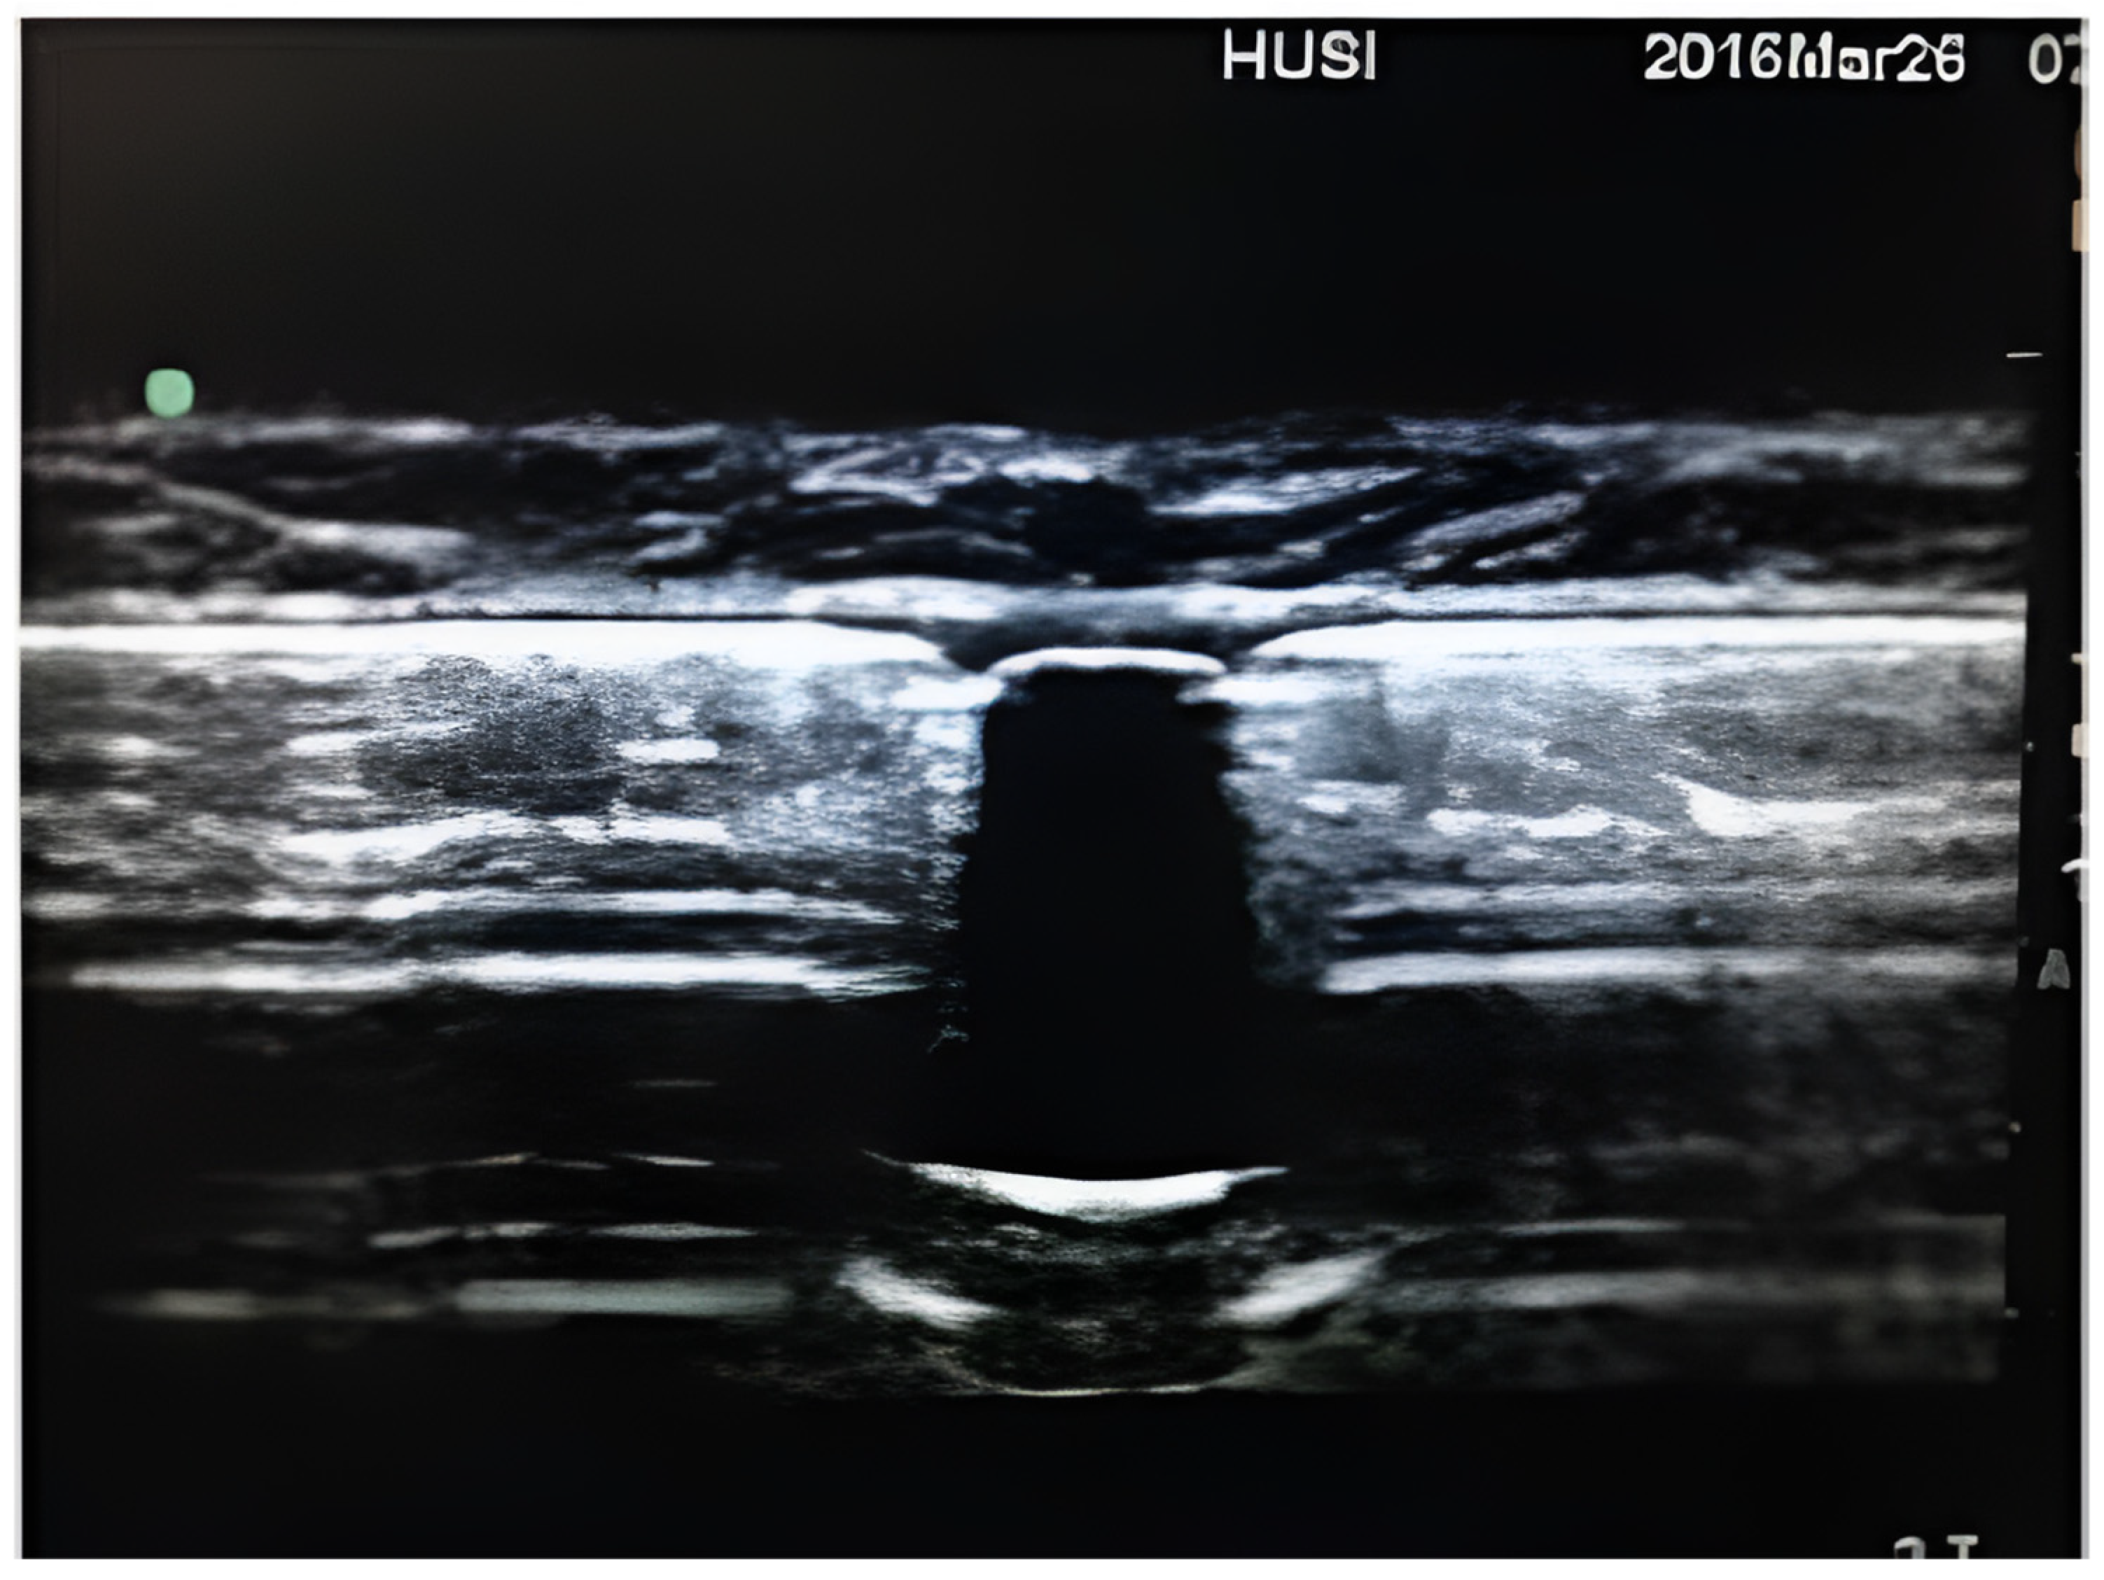

| Saulino et al., 2014 [11] | Descriptive study of intrathecal infusion pumps | To demonstrate the unique sonographic characteristics of intrathecal infusion pumps. | Intrathecal infusion pumps were analyzed outside the human body. They describe the sonographic characteristics of the pumps, highlighting that the refill port is anechoic, in contrast to the pump’s surface, which is hyperechoic. | The programmable intrathecal infusion systems have a unique sonographic appearance that could be used for refilling them. |